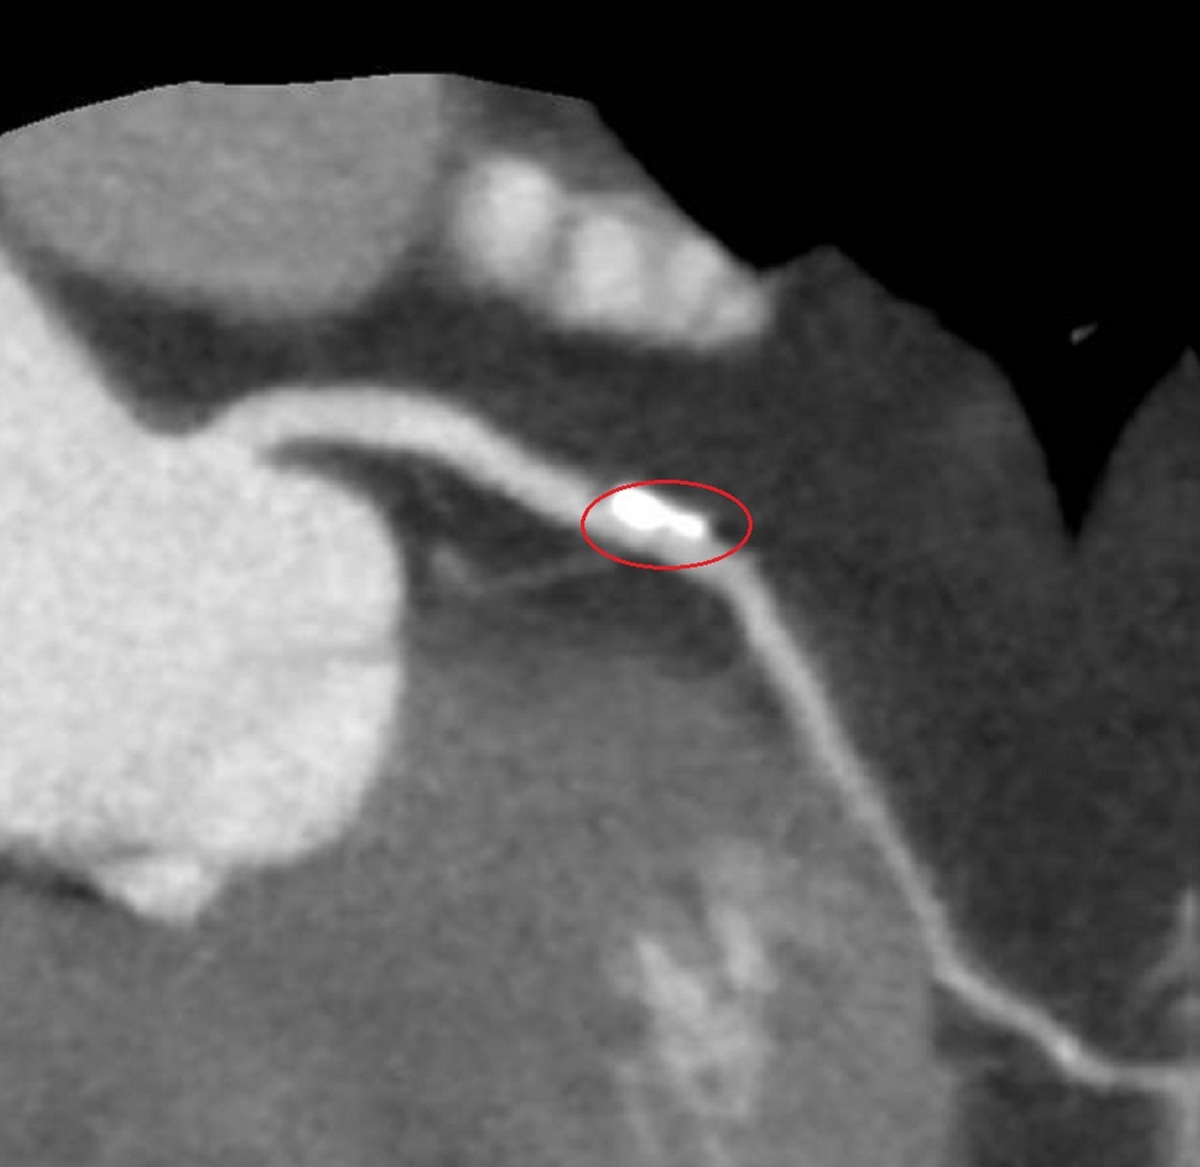

▲70歲盧女士胸悶不適,經檢查發現其心臟冠狀動脈有一處約70%阻塞,且伴隨心肌缺血與血管鈣化。(圖/彰化醫院提供)

李學林說,運動心電圖發現盧女士心血管缺血,電腦斷層發現左冠狀動脈的左前降支有一處約70%阻塞並鈣化,與病人共同決策,採IVL處理鈣化斑塊,再植入生物適應性支架,預期可達到最佳治療效果。